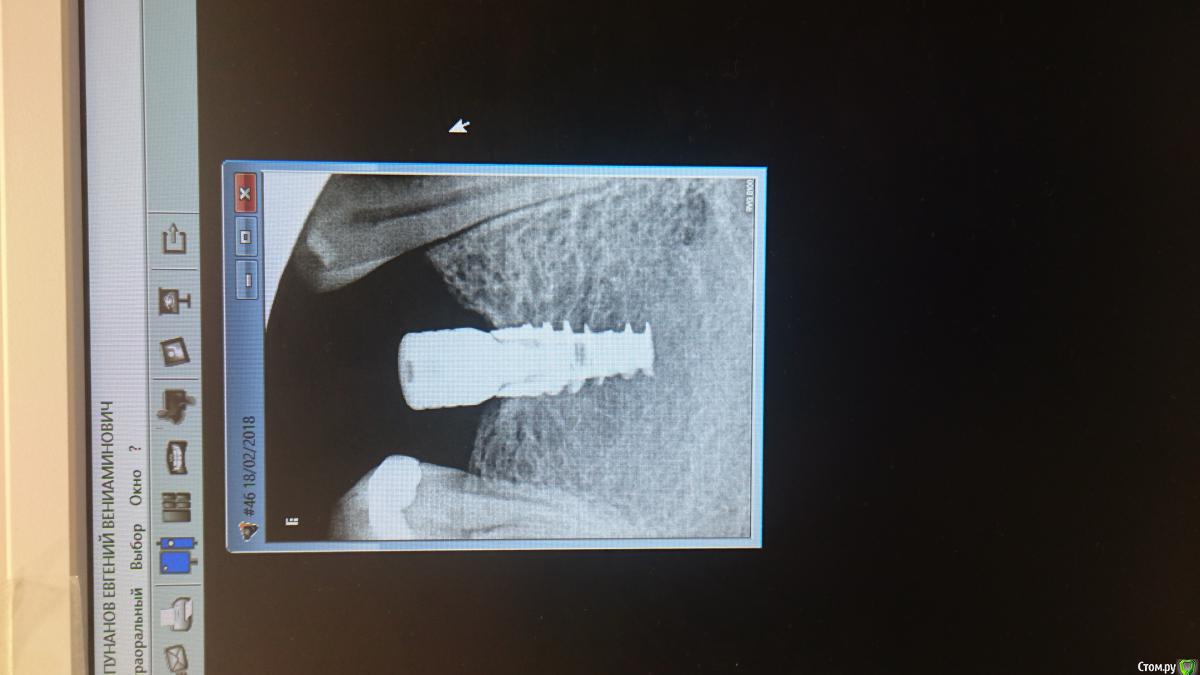

vadyasti Опубликовано 18 февраля, 2018 Поделиться Опубликовано 18 февраля, 2018 (изменено) Приветствую коллеги! Подскажите пожалуйста что за система импланта? Формик он альфы,а платформа импланта с зализанным шестигранником и очень глубокая.Со слов пац.Нобель. Ставили в Самаре 5лет назад. Клиника ДентАрт. Склоняюсь к Нобель Коникал конекшн. Изменено 18 февраля, 2018 пользователем vadyasti Ссылка на комментарий

krokomot Опубликовано 18 февраля, 2018 Поделиться Опубликовано 18 февраля, 2018 похоже на альфа био SPI Ссылка на комментарий

vadyasti Опубликовано 19 февраля, 2018 Автор Поделиться Опубликовано 19 февраля, 2018 (изменено) Это не Израиль и ему подобные. Нобель актив Коникал конекшн. Изменено 19 февраля, 2018 пользователем vadyasti Ссылка на комментарий

DrNice Опубликовано 19 февраля, 2018 Поделиться Опубликовано 19 февраля, 2018 Очень похоже на SPI Ссылка на комментарий

red_butler Опубликовано 20 февраля, 2018 Поделиться Опубликовано 20 февраля, 2018 похоже на альфа био SPI Очень похоже на SPI +1 Ссылка на комментарий